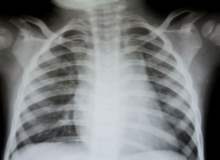

Reflü, mide asidinin ve mide sularının boğazdan mideye giden kanal boyunca tekrar yukarı çıkması anlamına gelir. Mide ekşimesine bu neden olur. Eğer haftada en az iki defa mide ekşimesi oluyorsa, buna mide ve yemek borusunun birlikte iltihabından kay